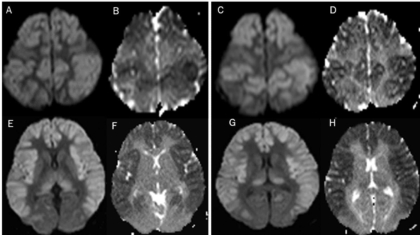

18 year old man was found unconscious. History of excessive somnolence, ataxia and fatigue past 5 days. No history of fever or seizures. History of head injury following road traffic accident a year back and was on prophylactic sodium valproate therapy regularly